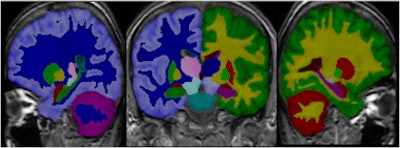

PredictAD aims to extract biomarkers from heterogeneous patient data and integrate them for objective and evidence-based diagnostics. For example its reasearch team is exploring how MRI can be used to measure atrophy in the mediotemporal lobe, which is recognized as a hallmark of Alzheimer's.

To meet this need, the PredictAD team has developed tools for measuring the size of the hippocampus, the atrophy rate of the hippocampus, and two approaches based on comparing patient data with previously diagnosed cases available in large databases. PET is also being studied in the project. A novel tracer developed recently especially for diagnostics of Alzheimer's disease provides promises for very early diagnosis of the disease.